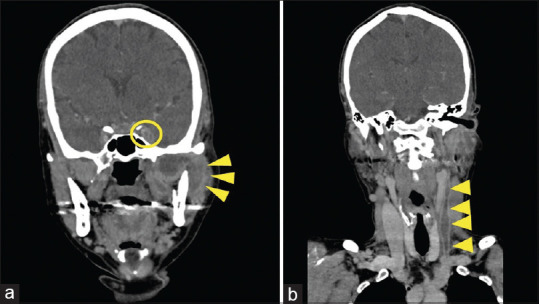

勒米尔综合征是一种罕见的疾病,以颈内静脉血栓性静脉炎和远处器官转移为特征。该病发生在喉部或牙齿部位的厌氧菌感染之后;中枢神经系统受累的情况并不多见。一名 50 岁的妇女出现意识障碍。发病前,她因牙痛接受了数天的牙科治疗。对比增强计算机断层扫描(CT)显示头颈部有脓肿,颈内静脉有大量血栓,诊断为莱米埃尔综合征。经过手术引流和抗菌治疗后,症状有所好转,患者于第 58 天出院。在这个病例中,由于大量脑静脉血栓导致静脉充血,并发了静脉中风,从而并发了莱米埃尔综合征。莱米埃尔综合征患者可能因血栓导致静脉中风,磁共振成像或 CT 静脉相成像可帮助诊断。

Lemierre's syndrome is a rare disease characterized by thrombophlebitis of the internal jugular vein and metastasis to distant organs. It occurs after an anaerobic infection of the larynx or dental region; the central nervous system involvement is infrequent. A 50-year-old woman presented with impaired consciousness. She had undergone several days of dental treatment for a toothache before presentation. Contrast-enhanced computed tomography (CT) revealed a head-and-neck abscess and a massive thrombus in the internal jugular vein, and a diagnosis of Lemierre's syndrome was made. After symptoms improved with surgical drainage and antimicrobial therapy, the patient was discharged on day 58. In this case, Lemierre's syndrome was complicated by a venous stroke caused by venous congestion due to a massive cerebral venous thrombus. Venous stroke due to thrombi may occur in patients with Lemierre's syndrome, and magnetic resonance imaging or CT with venous phase imaging may aid in the diagnosis.